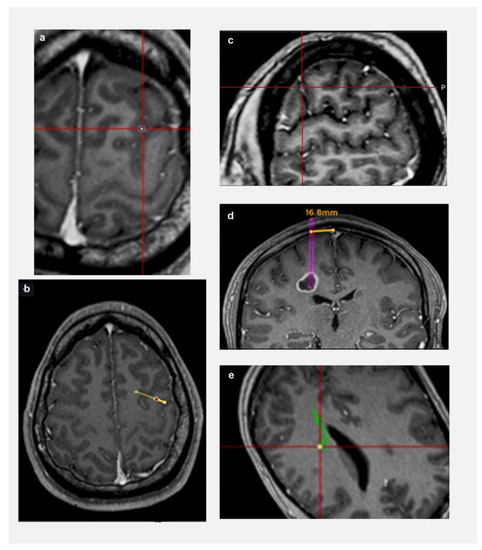

2. Methods